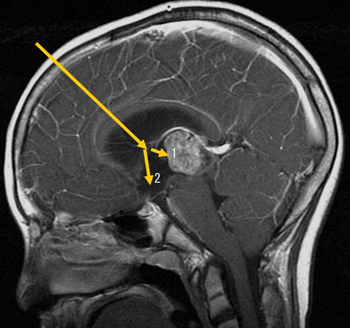

• 図2.内視鏡を用いた水頭症手術(第3脳室底開窓術)と腫瘍の生検術

矢印のように内視鏡を挿入し腫瘍の一部(1)を切除して診断をしたり、第3脳室の床に開窓(2)して水頭症を治したりします。

もう一つ脳室内腫瘍と水頭症の治療(図2)でも大変効果を上げています。頭の中には脳を衝撃などから守っている髄液と言う水が流れていますが、この水が腫瘍などでせき止められて溜まりすぎると水頭症という病気になります。内視鏡を頭の中の溜まった水の中にさして髄液の流れ出るバイパスを作ったり、腫瘍の一部を取って腫瘍の種類を診断したりして化学療法や放射線治療などの最善の治療法を選択できるようになりました。こうすることによって開頭手術をしないで済む場合も多く、一部の脳室内の腫瘍では内視鏡単独で摘出することもできるようになりました。